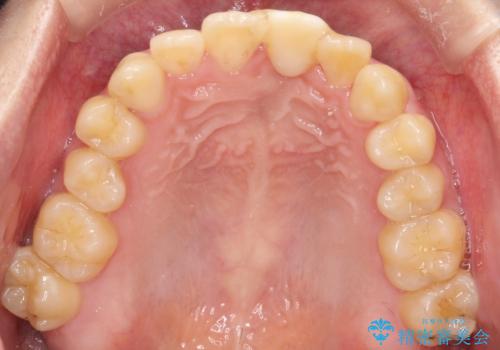

前歯の開咬とシザーズバイトを改善|インビザライン矯正

- 治療計画

前歯が噛まないため咀嚼が困難で、シザーズバイトにより噛み合わせに不調を感じていました。インビザラインを用いて、透明なマウスピースによる目立ちにくい矯正治療を実施。奥歯のシザーズバイトを改善した後、前歯の歯列を緻密に調整し、噛み合わせを整えました。定期的なマウスピース交換を通じて徐々に歯列が改善され、治療終了後には前歯が正常に咬合するようになり、噛み合わせの機能性と審美性が共に向上しました。